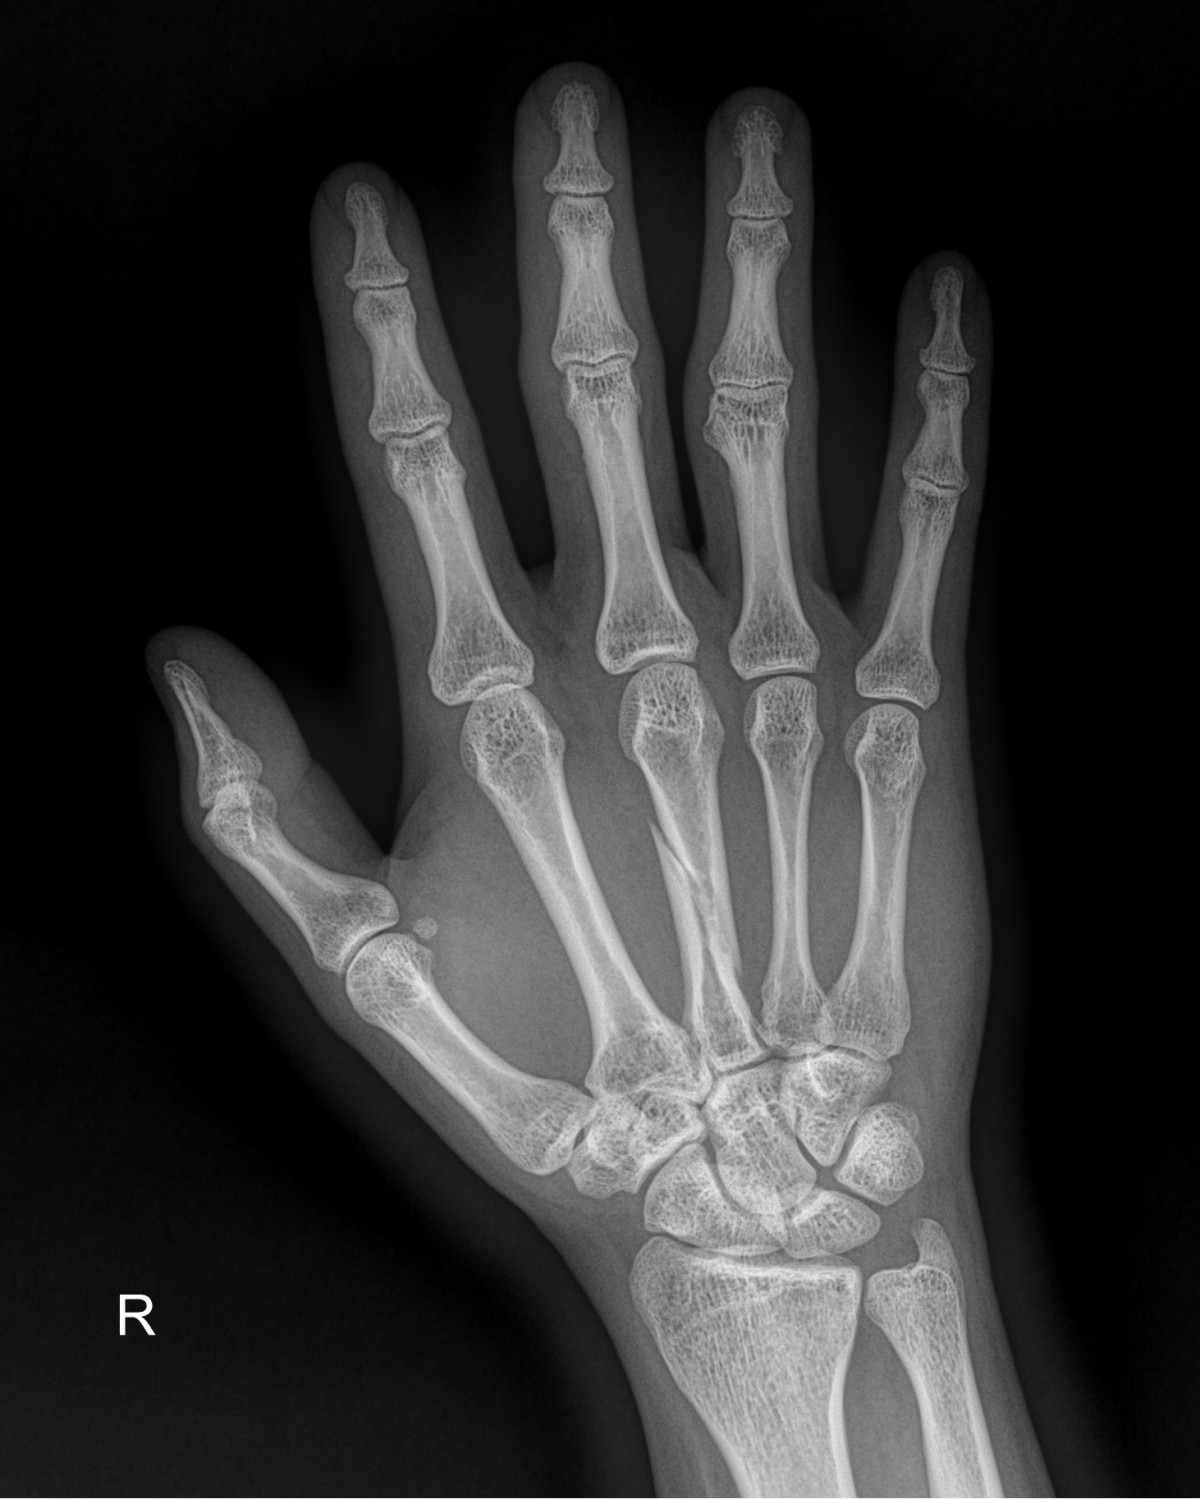

정지영원장님 손등 골절 수술 박준O 환자

작성자 최고관리자 댓글 0건 조회 816회 작성일 25-01-13 17:02

58490d3b1e200cf11df1ea881291f176_1736755361_0161.jpg